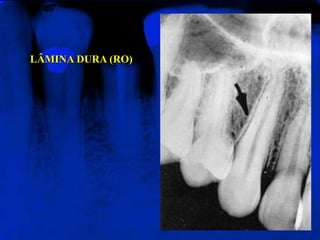

LÂMINA DURA (RO)Representa a porção da parede do alvéolo onde se inserem as extremidades externas das fibras periodontais. Apresenta-se radiograficamente como uma linha radiopaca fina que se continua com as cristas ósseas alveolares.

LÂMINA DURA (RO)Representaa porção da parede do alvéolo onde se inserem as extremidades externas das fibras periodontais. Apresenta-se radiograficamente como uma linha radiopaca fina que se continua com as cristas ósseas alveolares.